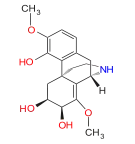

Others

- 1-Nitroaknadinine * 14-episinomenine

- 5,6-Dihydronorsalutaridine

- 6-Keto Nalbuphine

- Aknadinine

- Butorphanol

- Cephakicine

- Cephasamine

- Cyprodime

- Drotebanol

- Fenfangjine G

- Ketorfanol

- Nalbuphine

- Nalbuphone

- Tannagine

Structures

| Other Morphinans | ||||

|---|---|---|---|---|

1-Nitroaknadinine 1-Nitroaknadinine |

14-episinomenine 14-episinomenine |

5,6-Dihydronorsalutaridine 5,6-Dihydronorsalutaridine |

6-Keto Nalbuphine 6-Keto Nalbuphine |

Aknadinine Aknadinine |

Butorphanol Butorphanol |

Cephakicine Cephakicine |

Cephasamine Cephasamine |

Cyprodime Cyprodime |

Drotebanol Drotebanol |

Fenfangjine G Fenfangjine G |

Nalbuphine Nalbuphine |

Sinococuline Sinococuline |

Sinomenine Sinomenine |

Tannagine Tannagine |